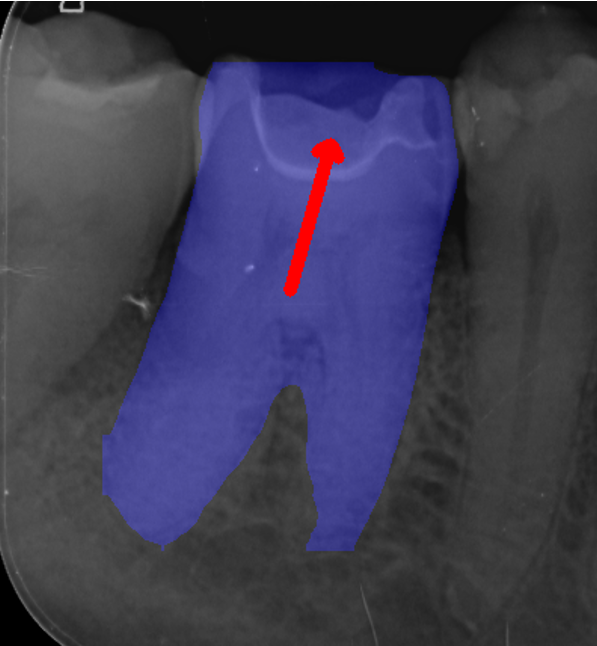

The initial stage of the post-processing module estimates the orientation of each tooth object from predicted tooth segmentation masks, in Figure 4(b). We first refine the predicted binary mask by retaining only the largest connected component, from which the boundary pixels are extracted using the Canny edge detector. Second order central moments [45] are then calculated from the edge representation of a tooth mask, where the principal axis of the tooth is then derived, giving us the orientation of the tooth mask normalised between 90-90^{\circ} and 9090^{\circ}. This tooth orientation acts as a rotation index for subsequent tooth alignment and for evaluation purposes.

Refer to caption

(a) Predicted Keypoints/Masks

(b) Tooth Orientation

(c) Mask Partitioning

(d) Edge Association

(e) Mask-Keypoint Matching

(f) Mesial/Distal Determination

Figure 4: Handmade example diagrams, with synthetic data, depicting each stage of the post-processing module overlaid on Image104.

Once the orientation is derived, each tooth mask is split into left and right halves, by constructing a rotated bisector through its centroid, in Figure 4(c). This step ensures that all subsequent anatomical assignments are performed relative to the true orientation of each tooth independently, rather than the image axes.

The post-processing module then determines the mask edge pixel associations for each predicted keypoint to the anatomical boundaries of each predicted tooth. The lowest Euclidean distance for a given keypoint to each closest edge pixel for all mask halves is chosen. This provides a geometric link between anatomical landmarks and boundary structures, allowing precise localisation relative to tooth edges. This step can be seen in Figure 4(d), where the red point is a single example of a predicted keypoint, the green point is the closest edge pixel for the closest segmentation mask halve, and yellow points are the closest edge pixel for all other mask halves.

To resolve which mask best corresponds to a given group of keypoints, the average distance between visible keypoints and their associated edges is computed. The mask with the smallest mean distance is selected as the most appropriate match, effectively filtering out false positive masks.

At this stage we have many keypoint-edge associations for all predicted keypoints, where each keypoint has an association for every predicted left and right side segmentation mask in the image. The post-processing module then proceeds to match each predicted keypoint group with its most likely associated predicted mask, by choosing the mask with the lowest average distance across all visible keypoints in the group. This process filters out false postive mask predictions, by disregarding non matched masks. This process can be seen in Figure 4(e), where green points are the closest edge pixel for a given predicted red keypoint, and yellow keypoints are the edge pixels for the matched segmentation mask if that keypoint’s closest edge pixel is not with the matched mask.

Finally, the post-processing module determines which sides of the image are mesial and distal. These are determined by distance based majority voting across visible keypoints for mesial and distal related keypoints. Each keypoint is assigned to the closest side of the matched mask, and votes are accumulated by anatomical keypoint class. The side with the most votes for mesial keypoints defines the mesial half, with the distal side assigned as its inverse. The final post-processed keypoints replace raw predictions when appropriate, ensuring consistent anatomical alignment across all teeth, as shown in Figure 4(f).